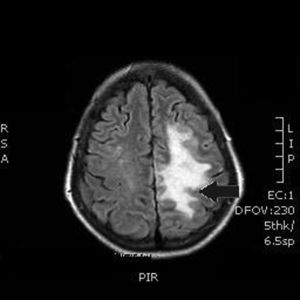

Our patient was a 55-year-old woman, a smoker (15 cigarettes/day) who presented chronic obstructive pulmonary disease, depressive disorder, and systemic lupus erythematosus (with lupus nephritis and antiphospholipid syndrome). The patient was receiving escitalopram, salbutamol, and acenocoumarol. She was admitted due to abdominal pain of 10hours’ progression, due to a duodenal perforation. She underwent emergency surgery, with suture and Graham patch of the anterior wall of the duodenal bulb by midline laparotomy. During the intervention, a CVC had to be placed in the right internal jugular vein (guided by ultrasound) to be used for parenteral nutrition in the immediate postoperative period. The procedure was uneventful and the patient was transferred to the recovery room, where she stayed for 12hours with no complications and started parenteral nutrition. She was subsequently transferred to an admission ward. At 48hours, immediately after replacement of the parenteral nutrition bag with the patient in a seated position, she presented an abrupt decrease in the level of consciousness, with quadriparesis, gaze deviation to the left, and facial droop. Arterial blood pressure, heart rate, and oxygen saturation values were normal. An emergency cranial CT scan (Fig. 1) revealed pneumocephalus with intraparenchymal air bubbles in the border zone of the middle cerebral artery and left anterior cerebral artery, and in arachnoid sulci of the left parietal convexity, compatible with air embolism. When her level of consciousness recovered, the patient presented right-sided hemiplegia and dysarthria, and was transferred to be treated with hyperbaric oxygen. An MRI study performed at 48hours (Fig. 2) revealed an extensive area of vasogenic cerebral oedema compatible with acute/subacute ischaemic lesions. An echocardiogram showed no evidence of heart disease, valvulopathy, or intracardiac shunts. Despite 4 sessions of treatment in a hyperbaric chamber with administration of 100% oxygen at 2.2 atmospheres for 60minutes, the patient showed no clinical improvement, with the right hemiplegia and dysarthria persisting. When she was discharged, the patient presented paresis of the right upper and lower limbs (3/5 in both) and hypoaesthesia, with altered positional sensitivity and inability to hold a standing position or walk, making her dependent in the activities of daily living. The Barthel Index score was 15/100.